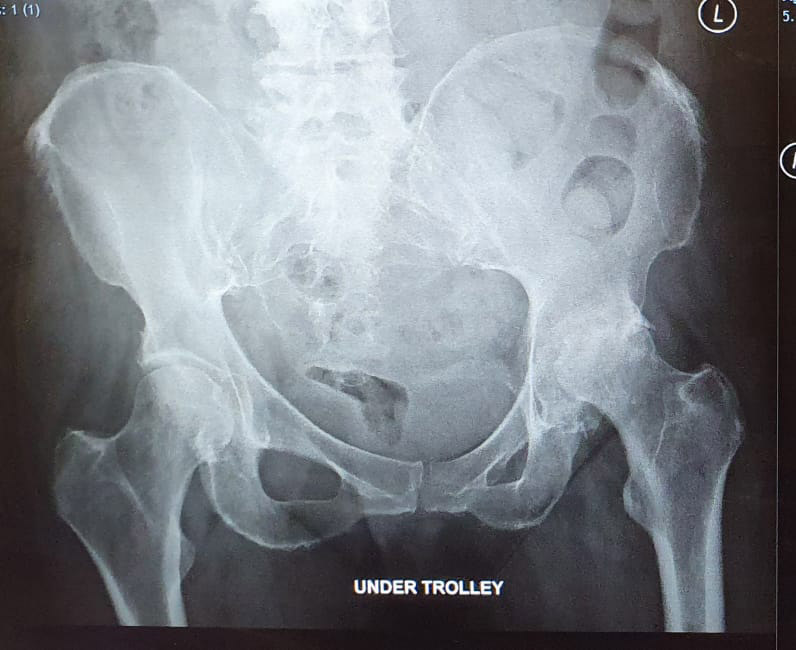

See below for some before and after X-rays of total hip replacement surgeries I have performed to treat Osteoarthritis. Drag the sliders to switch between the before and after images.

I am 7 weeks and 6 days post op, for a complicated left hip replacement. Essentially I had no socket for my left hip. Mr Magra virtually reconstructed my whole upper leg. The chronic pain beforehand meant I was unable to walk much more than 100m without intense pain. Post op I have completed in excess of 2 miles with 2 crutches and 1 mile with a single crutch and I am now starting tingling confidence to lose the crutches altogether. I honestly cannot tell you how much of a difference Mr Magra and his team have made to my life.